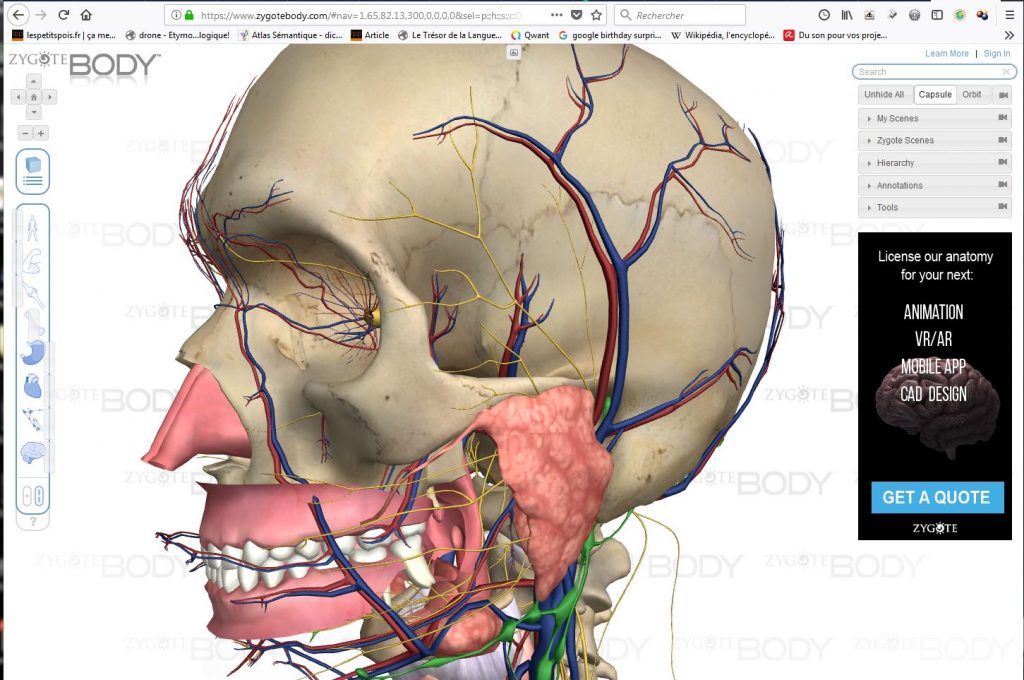

3/ Il est bien évidemment possible de zoomer et de tourner autour du modèle, directement avec la souris: